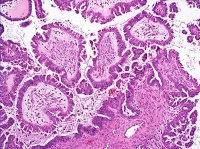

2、上皮性肿瘤:占卵巢肿瘤的50~70%,此中以浆液性肿瘤最常见,其次为粘液性肿瘤。以其构造学及细胞学特点,它们各有良性、交界性(低度潜伏恶性瘤)及恶性之分。上皮腺瘤占卵巢恶性肿瘤的90%。

1.良性,囊腺瘤和乳头状囊腺瘤,表面乳头状瘤,腺纤维瘤和囊腺纤维瘤。

2.临界恶性(低度恶性潜能) 囊腺瘤和乳头状囊腺瘤,表面乳头状瘤,腺纤维瘤和囊腺纤维瘤。

3.恶性腺癌、乳头状腺癌和乳头状囊腺癌,表面乳头状腺癌,腺癌纤维瘤和囊腺癌纤维瘤。